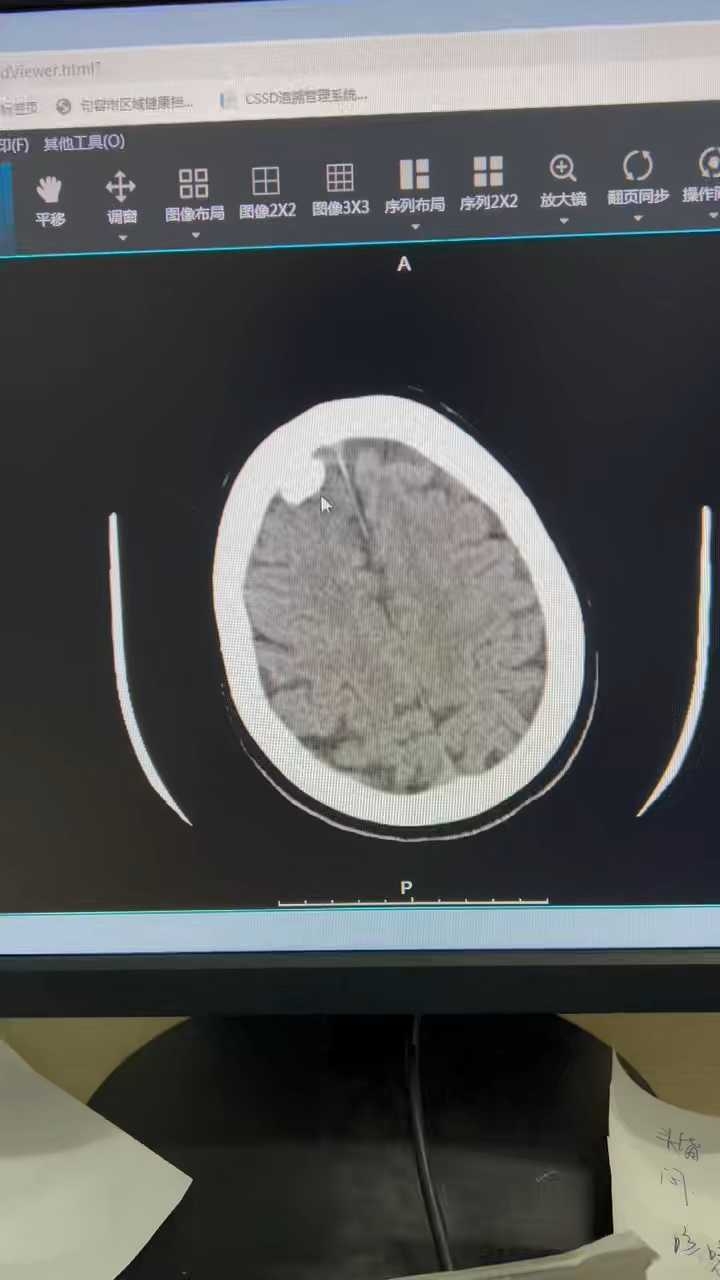

病例大佬们,这个ct考虑啥

全科医师 · 发布于 09-02 · 来自 Android · IP 江苏江苏